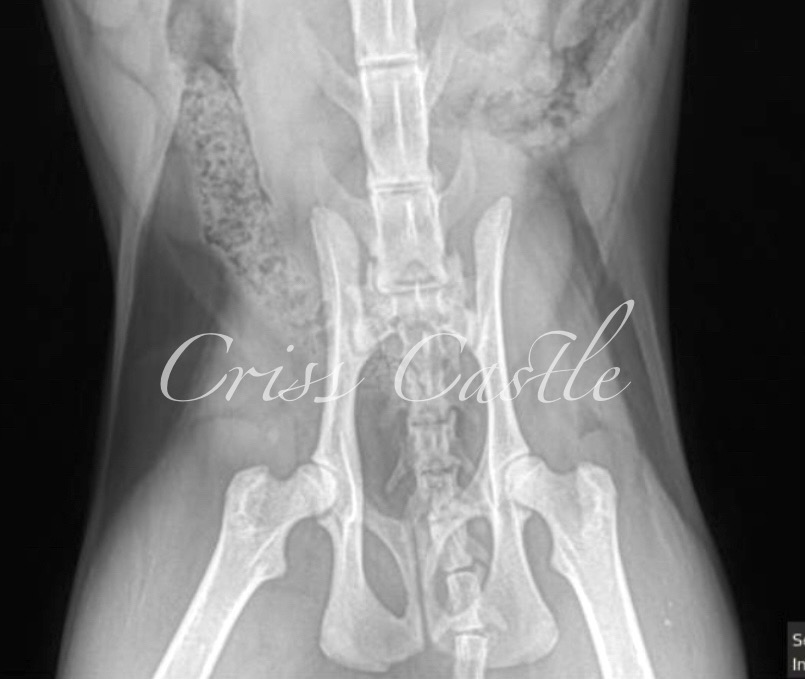

Hip X-Ray Results

Below are the current hip x-ray results for each Criss Castle breeding cat.

Note that as the cats continue to grow, this page may be updated with new results.